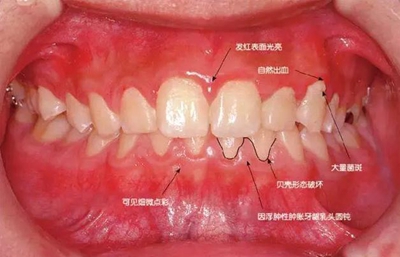

患牙齦炎的牙周組織的臨床圖像

22歲男性牙齦炎的臨床圖像

22歲男性,抽煙(1天約15根,煙齡5年)。刷牙狀態(tài)不佳。抽煙者特有的纖維性牙齦,未見發(fā)紅、腫脹。探針觸診,所有部位均出血。X線牙片未見骨吸收,診斷為牙齦炎。